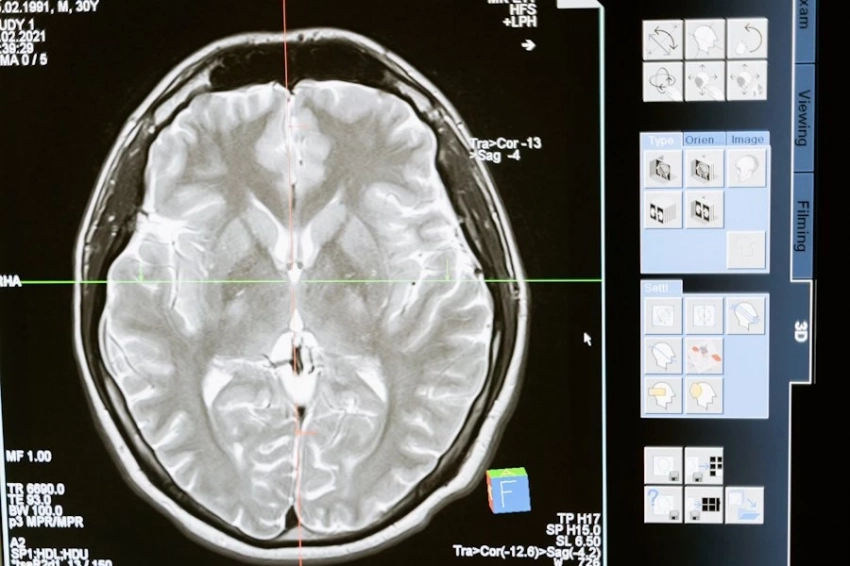

Китайские ученые выяснили, что недостаток сна негативно отражается на мозговой функции. Если недосып превращается в хронический, то снижается память, иные мыслительные способности. Повышается риск нейродегенеративных болезней.

Как сообщает журнал The Publications Division of the American Chemical Society, специалисты медицинского колледжа Биньчжоу выяснили, что хроническая нехватка сна приводит к падению уровня белка плейотрофина (PTN). Что вызывает дисфункцию нейронов с последующим развитием нейродегенеративных заболеваний.

В ходе лабораторных опытов на грызунах китайские эксперты доказали, что недосып провоцирует нарушения в гиппокампе, отвечающем за обучение и память.

Процесс развивается через снижение уровня плейотропина (PTN). Это белок, который кодируется геном PTN. А снижение уровня PTN нарушает функционал нейронов в гиппокампе, Дальше развиваются такие болезни, как Паркинсон, Альцгеймер и им подобные патологии.